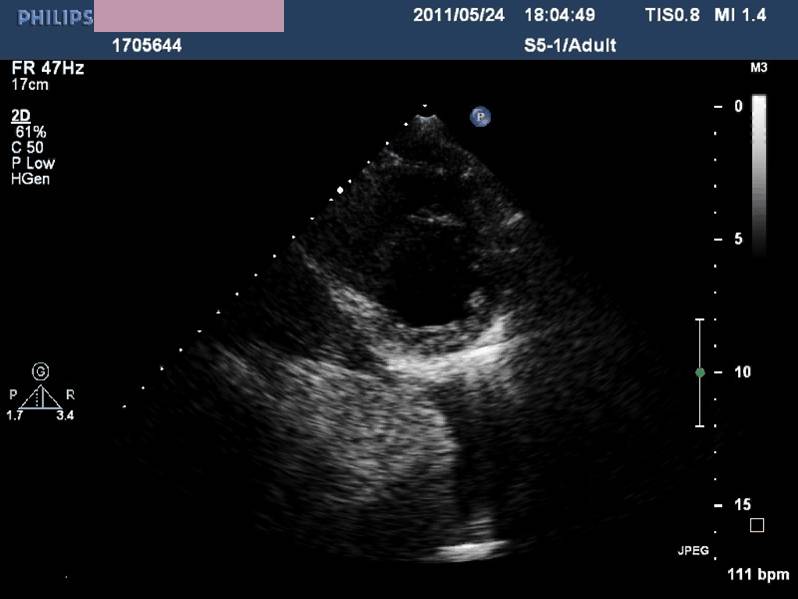

——床旁超声心动:节段性室壁运动异常,左房增大,轻度二尖瓣关闭不全,左室收缩功能减低,LVEF 45%,少量心包积液

现病史-超声心动

急性左心收缩功能不全